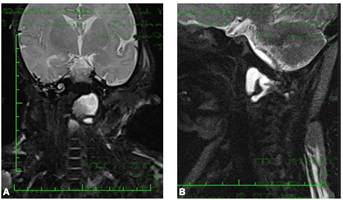

En cuanto a la imagenología se estudió con tomografía computada (TC) y resonancia magnética (RNM) a los 12 días de vida, donde se destacan hallazgos compatibles con meningitis complicada con isquemia y trombosis de los senos transversos y sigmoideos izquierdos; así como una colección retrofaríngea a izquierda de aproximadamente 20 x 9 x 15 mm la cual se extiende hacia región paravertebral a izquierda comprometiendo la primera vértebra cervical (C1) sin extensión al canal espinal (Figura 1).

Figura 1: A, B: Corte coronal y sagital en secuencia T1 de RNM, se observa colección retrofaríngea a izquierda de aproximadamente 20 x 9x 15 mm la cual se extiende hacia región paravertebral a izquierda comprometiendo la primera vértebra cervical.